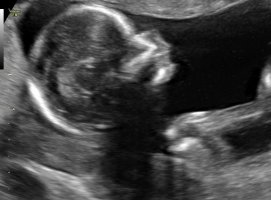

Men tror ikke jeg klarer se nuben her dessverre